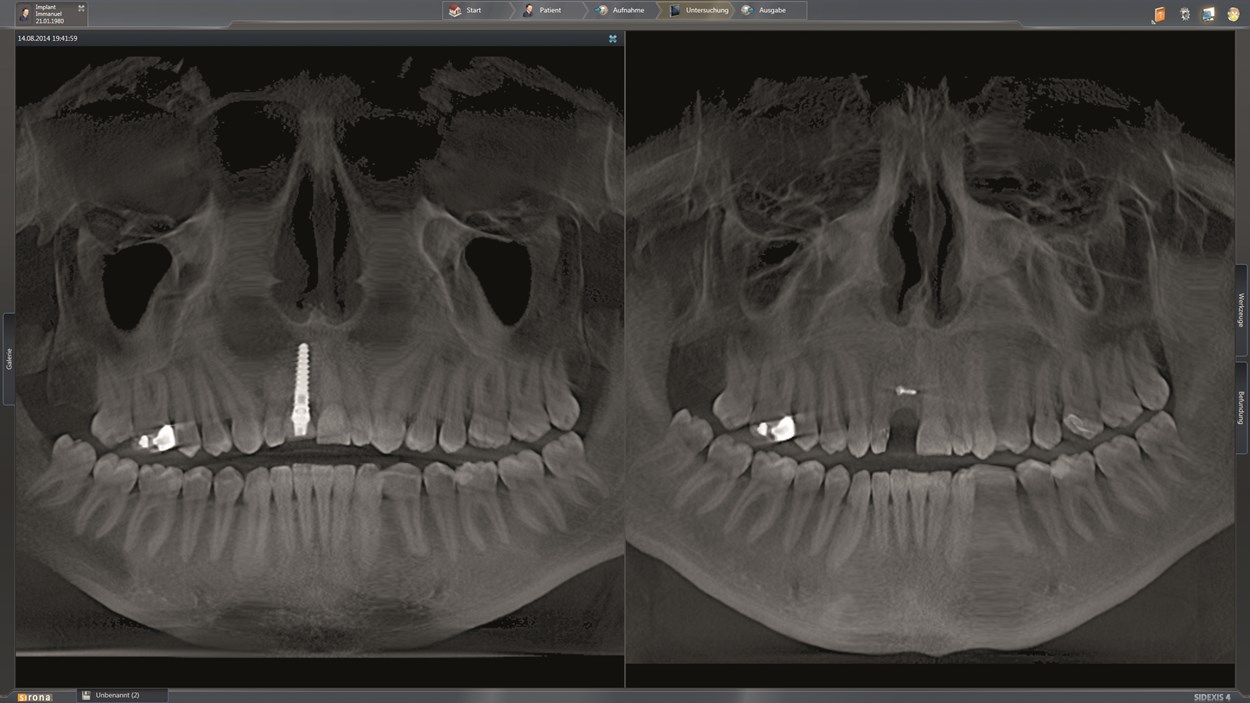

Фотографии и изображения КТ аппарата ORTHOPHOS SL

Раздел: Мудрость в фокусе